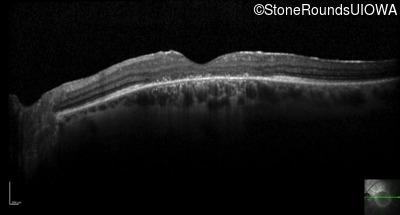

Optical Coherence Tomography - Right - 10/125 +1 sc

Exemplar / OCT Stack

OCT Stack